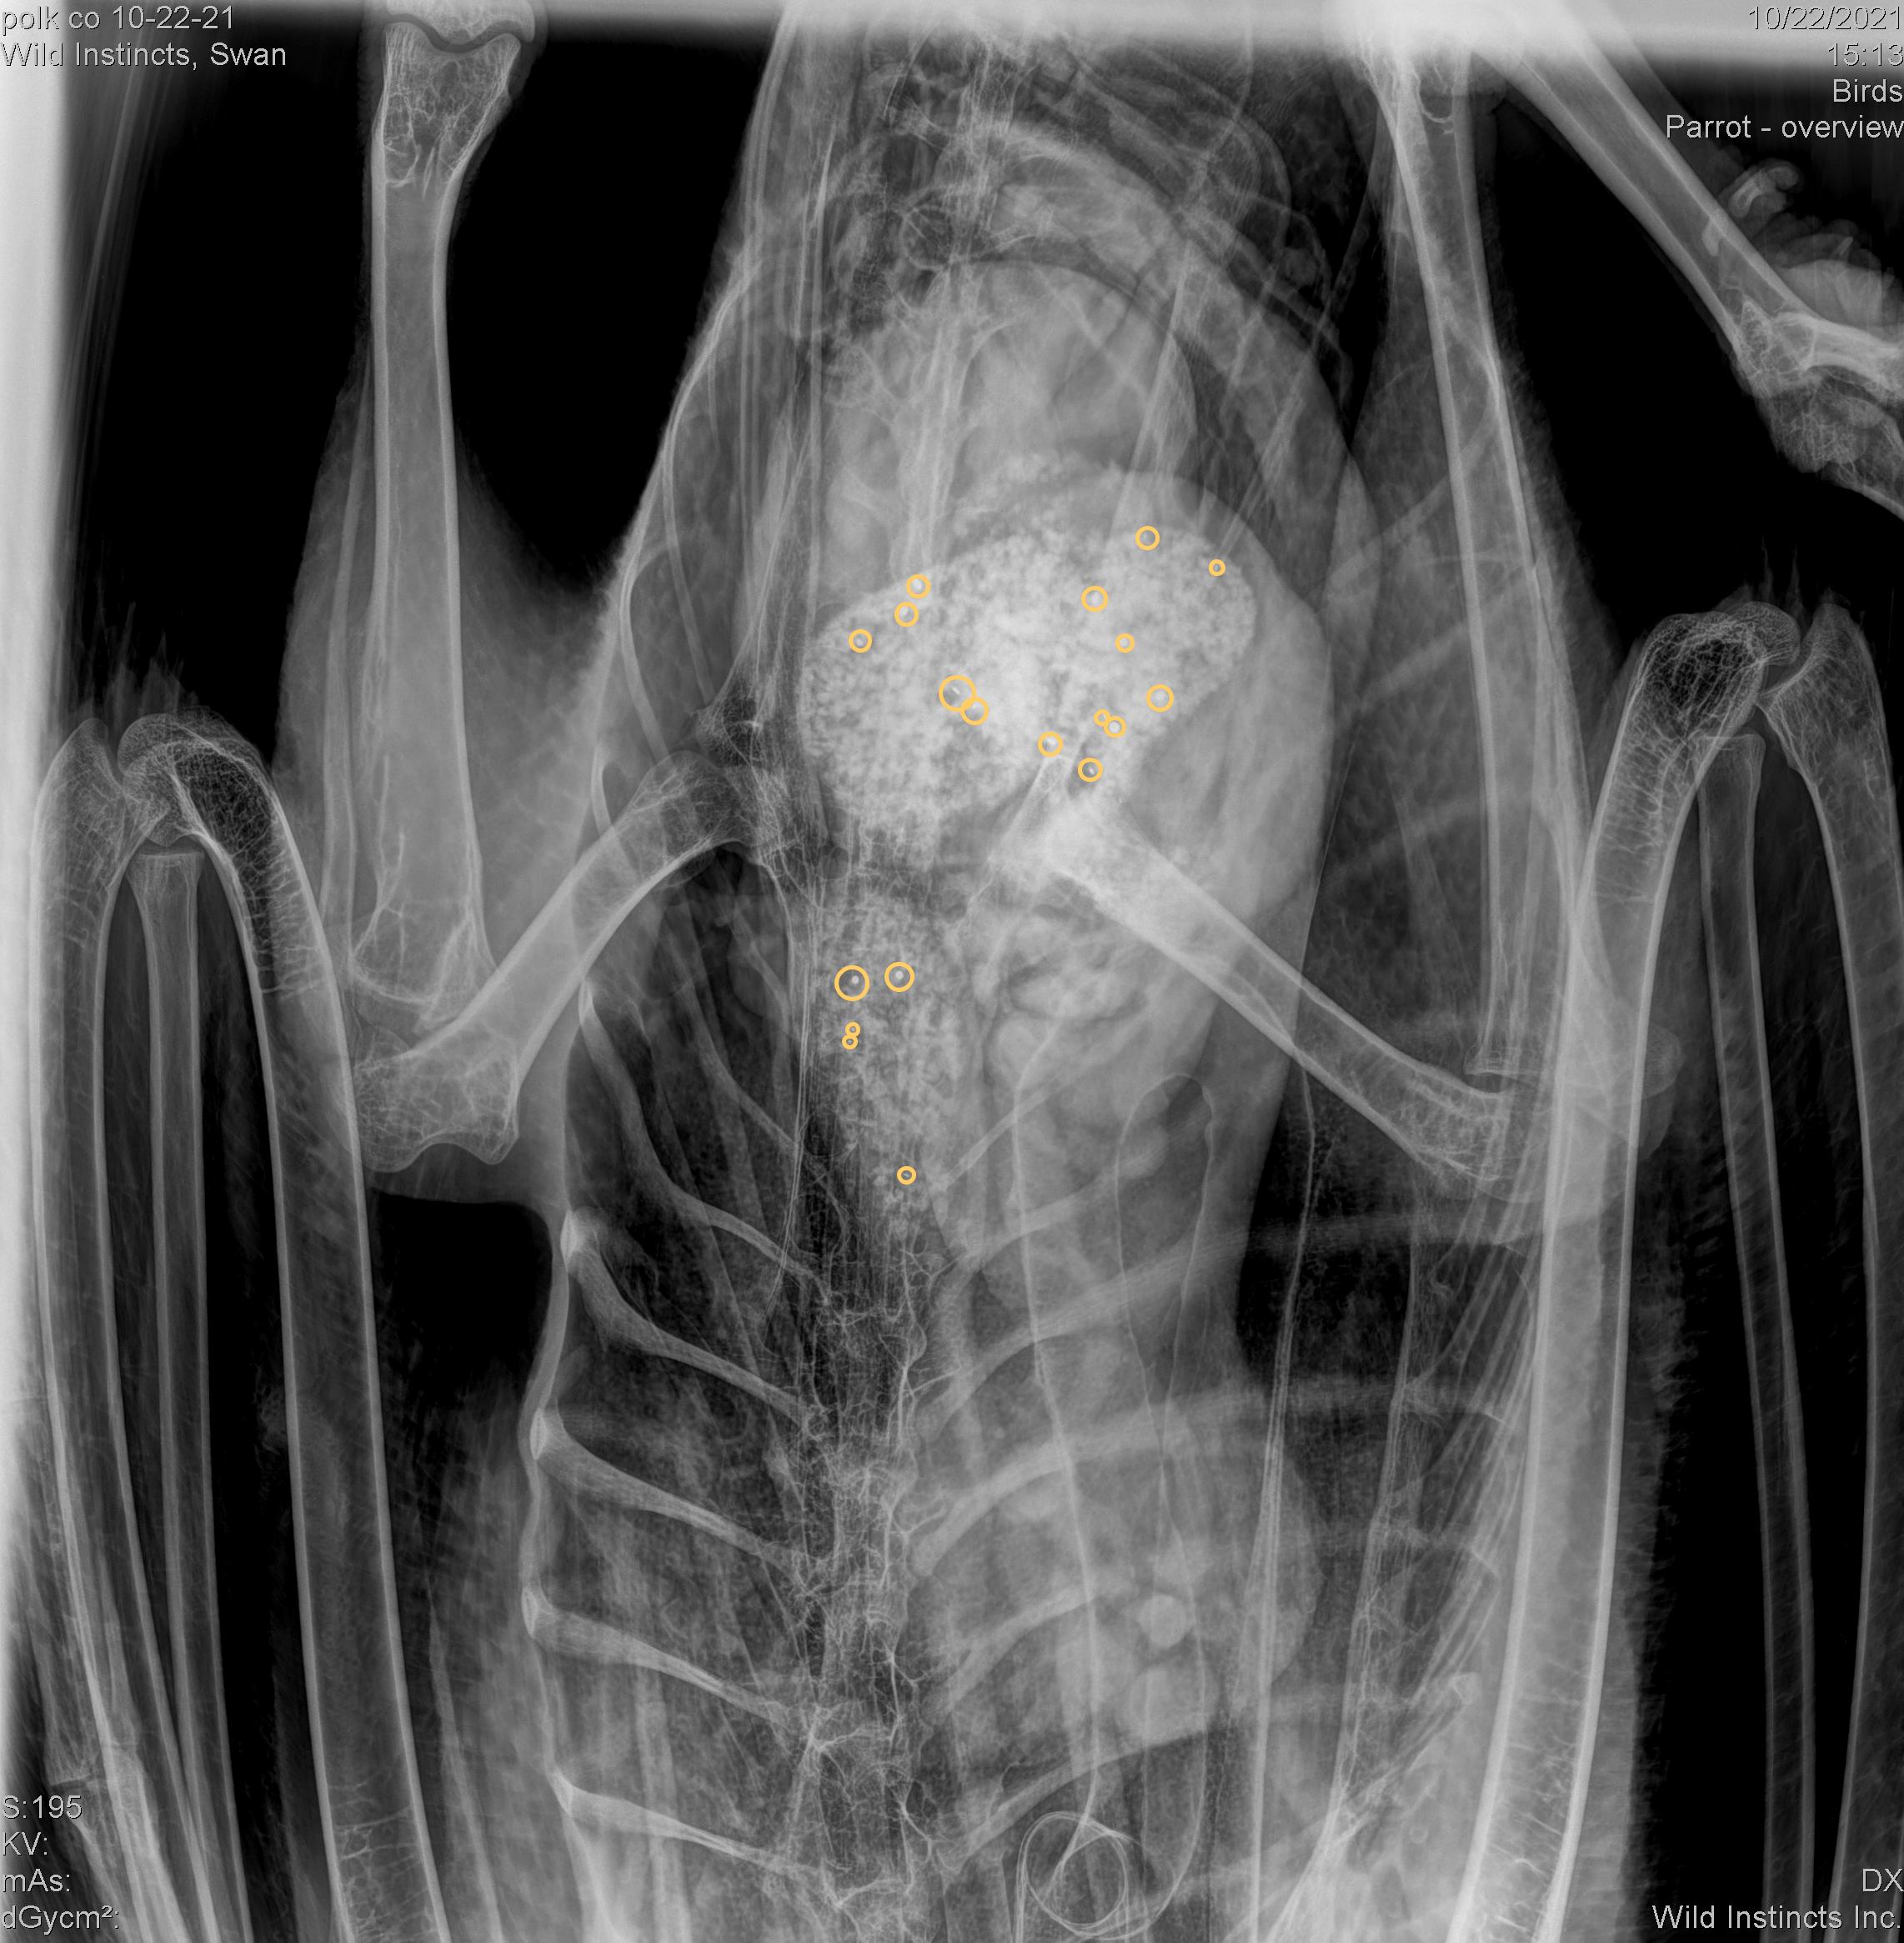

Over 19 discernible lead fragments were visible on the x-ray taken upon admission.

During the past 45 days, several x-rays have been taken to determine the status of the lead in the digestive tract as well as several blood lead level tests to monitor lead levels.